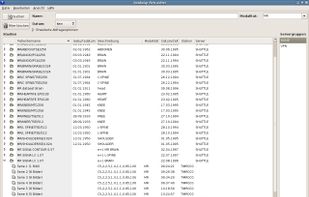

Aeskulap is a medical image viewer capable to load a series of special images stored in the DICOM format for review, query and fetch DICOM images from archive nodes (also called PACS) over the network.